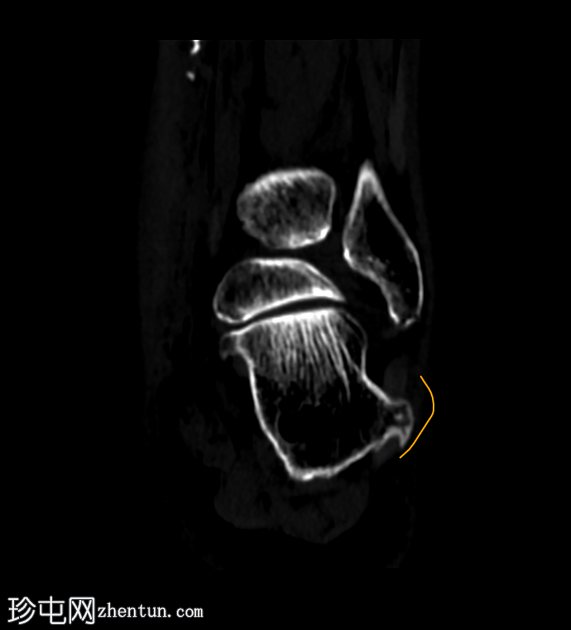

临床表现

跟骨外侧

疼痛

。

患者资料

年龄:65岁

性别:女

跟骨轴位CT

轴位

平扫

轴位骨窗